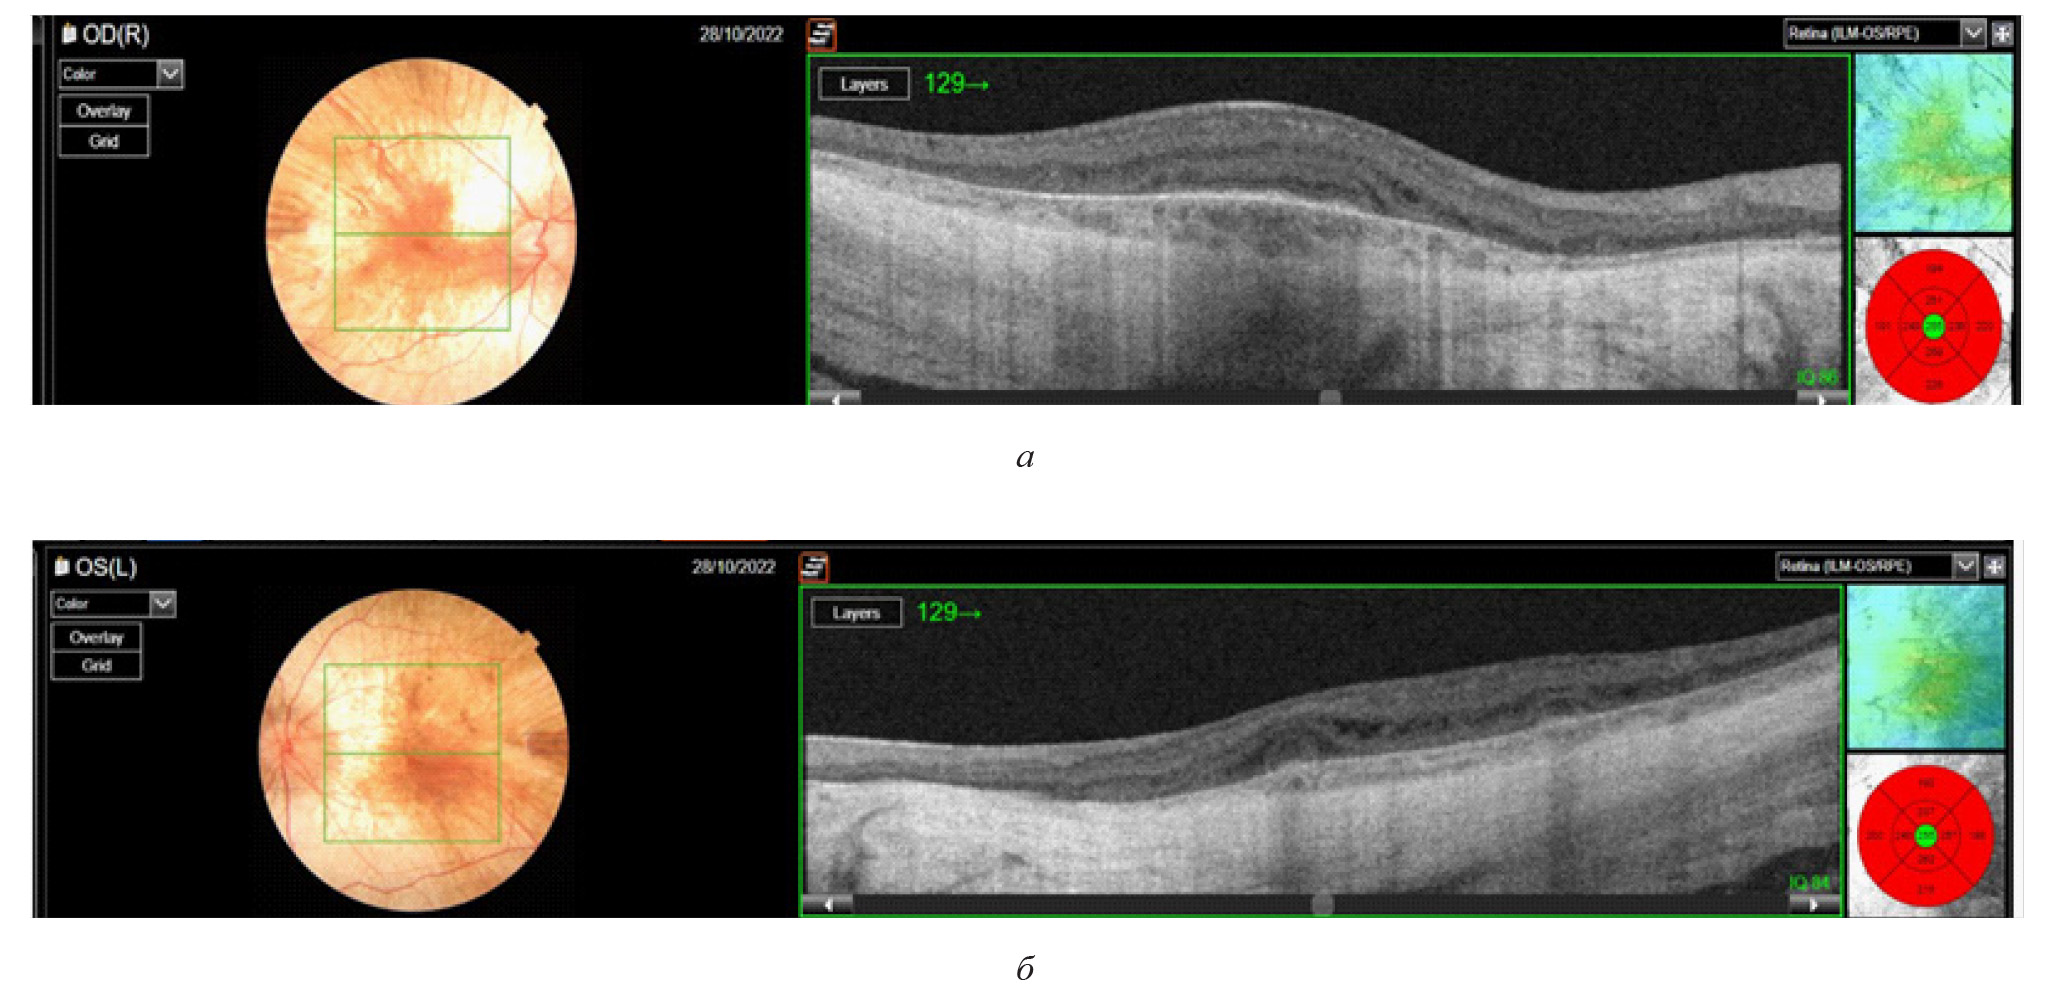

Были проведены следующие исследования: фоторегистрация глазного дна с помощью фундус-камеры оптического когерентного томографа Mirante (рис. 3 а, б), исследование аутофлюоресценции глазного дна (рис. 3 в, г), ОКТ макулярной зоны (прибор DRI OCT Triton) (рис. 4 а, б). По данным ОКТ определялось отсутствие линии сочленения наружных и внутренних сегментов фоторецепторов в фовеа, что является важным структурным маркером дегенеративных изменений сетчатки, при этом наблюдалась сохранность фоторецепторов в зоне фовеа. Эти результаты согласовались с клинической картиной хороидеремии и свидетельствовали о выраженных дегенеративных изменениях в сетчатке и сосудистой оболочке глаза. Сохранность фоторецепторов в зоне фовеа объясняла относительно высокое сохранение центрального зрения, несмотря на общую дегенерацию сетчатки. Пациенту была выполнена электроретинография ERG OU стандарт (Tomey EP-1000): амплитуда и латентность «а» волны была снижена при максимальном и колбочковом ответе, что свидетельствовало о нарушении функции фоторецепторов в центре и на периферии.

Рис. 3. Результаты обследования пациента Х.: а, б – цветное изображение правого и левого глаза с помощью оптического когерентного томографа Mirante в режиме SLO color 163; в, г – изображение глазного дна в режиме аутофлюоресценции (Heidelberg Spectralis): выраженная гипоаутофлюоресценция с центральным остаточным участком сохранного пигментного эпителия с фестончатыми краями

Рис. 4. Оптическая когерентная томограмма (прибор DRI OCT Triton) макулярной области сетчатки пациента Х.: а, б – нарушение трехслойной структуры наружных слоев сетчатки на всем протяжении скана, включая субфовеальную зону, кистозный макулярный отек в средних и внутренних слоях сетчатки, полное истончение сосудистой оболочки, вследствие чего визуализируется прилежащая склера